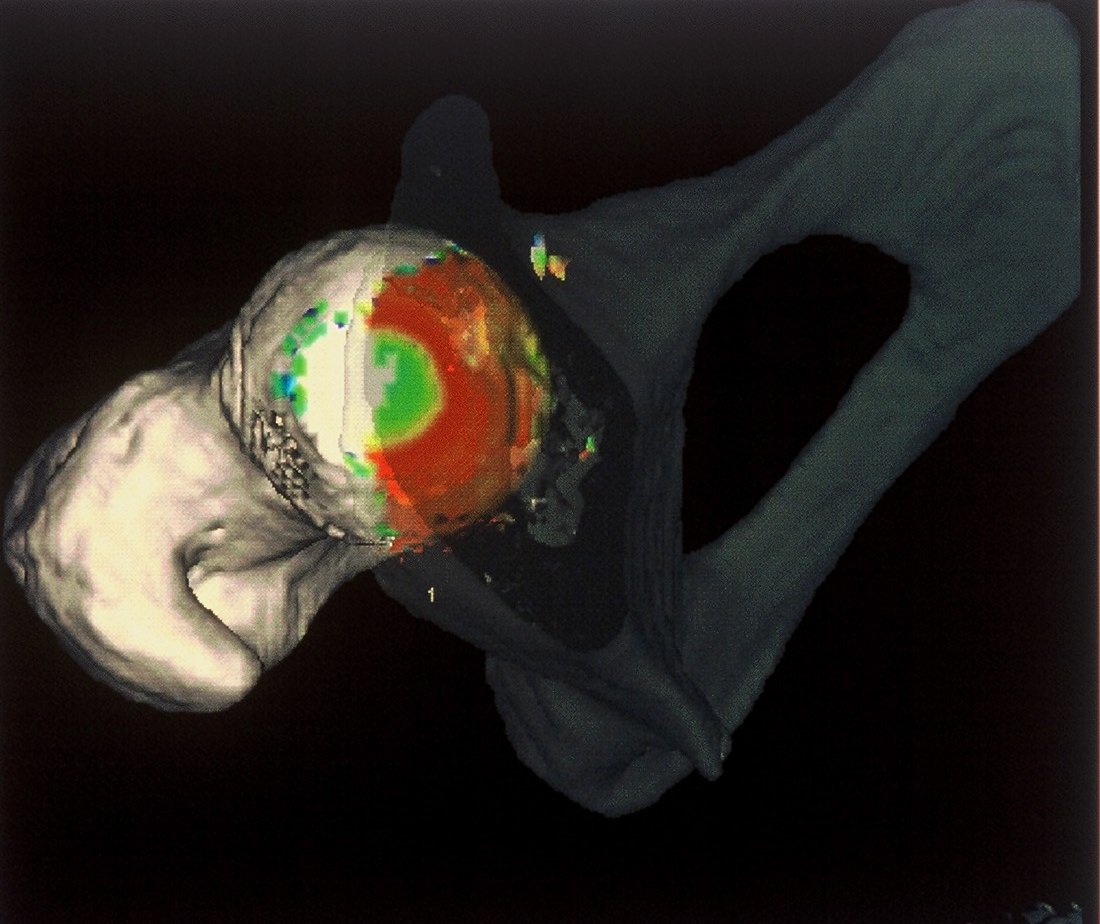

Das vorgestellte Verfahren liefert einen Ansatz für ein Operationsplanungssystem mit Hilfe dreidimensionaler Daten aufbauend auf CT-Daten des Beckenbereichs. |

Eingesetzt werden automatische Verfahren zur Segmentierung und Analyse der zweidimensionalen CT-Bilddaten. Sie basieren auf Regeln über die Form und Lage der gesuchten Objekte, deren Grauwertbereich und den Aufnahmeparametern des bildgebenden Verfahrens. Ziel ist die Entwicklung eines allgemeinen Ansatzes zur automatischen Segmentierung anatomischer Objekte aus medizinischen Volumendaten. Daneben werden Methoden zur interaktiven und automatischen Ergebnisklassifikation entwickelt, die in Abhängigkeit von den Anforderungen der nachbearbeitenden Analyseprogramme die aktzeptablen von den nicht-aktzeptablen Segmentierungsergebnissen trennen. |